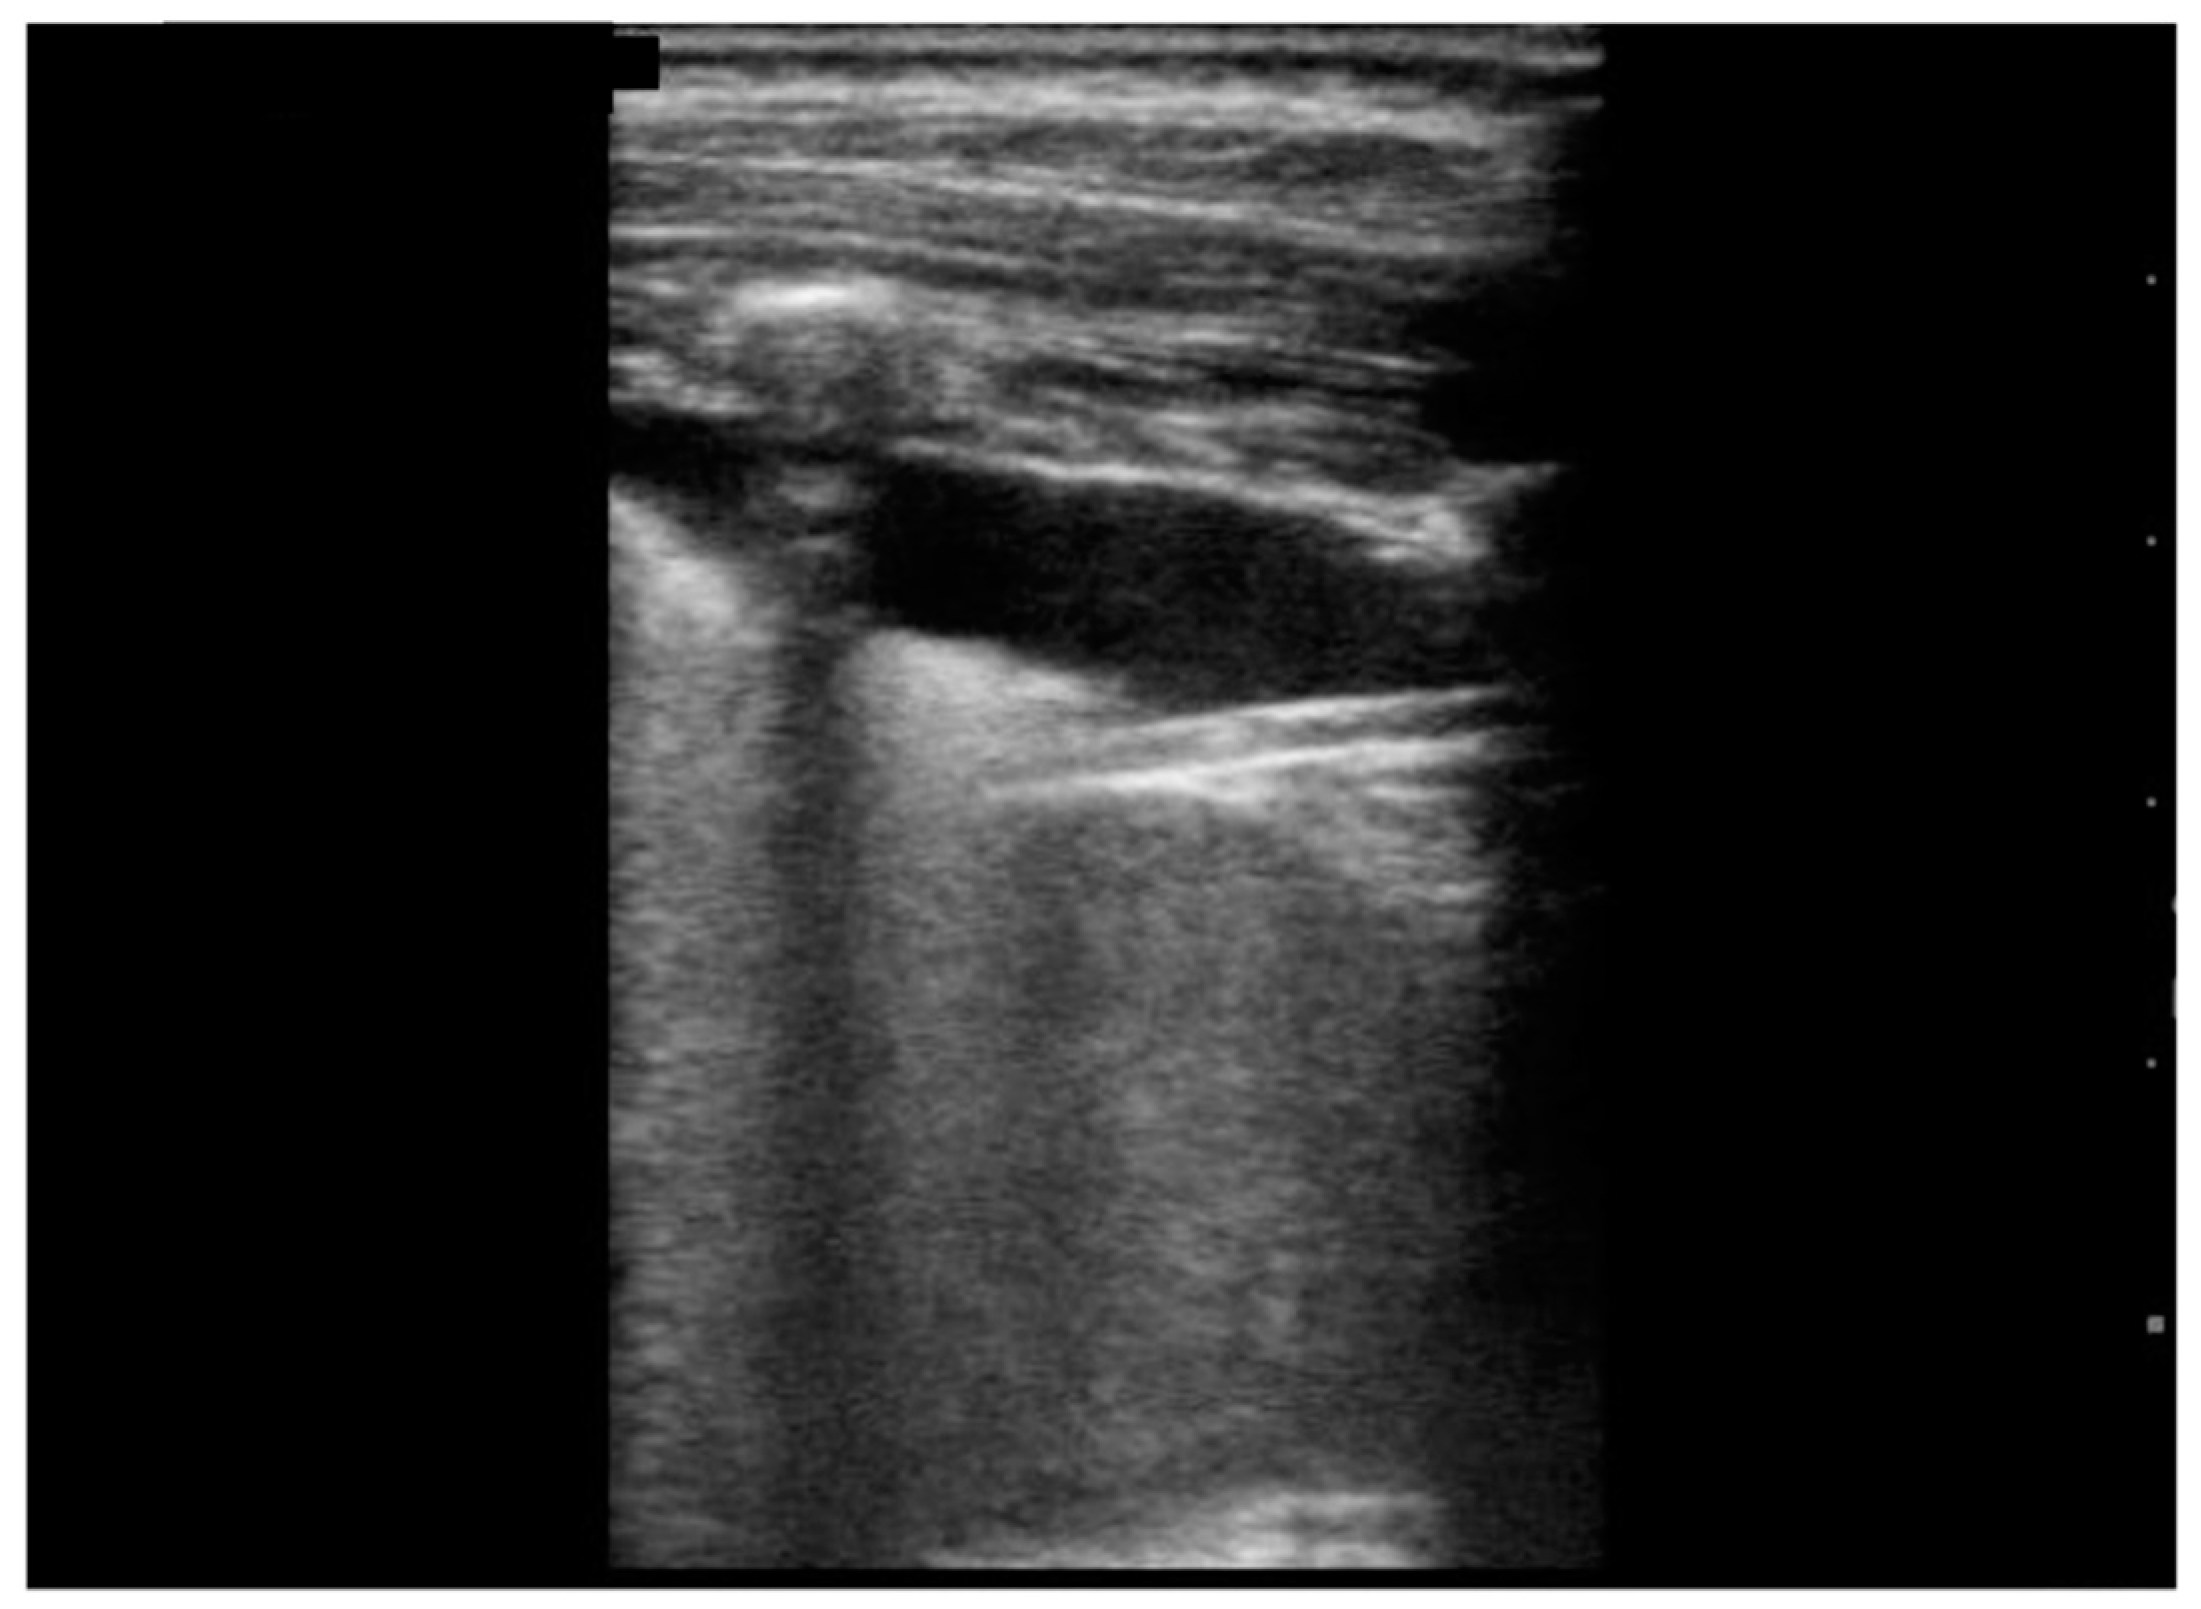

| Irregular/indented/broken pleural line, n (%) | 10 (100) | |

| B-lines, n (%) | 10 (100) | |

| Multiple/several B-lines, n (%) | 8 (80) | |

| White lung, n (%) | 5 (50) | |

| Sub-pleural consolidation, n (%) | 7 (70) | |

| Pleural effusion, n (%) | 9 (90) | |

| LUS score, mean ± SD | 10.5± 1.81 |